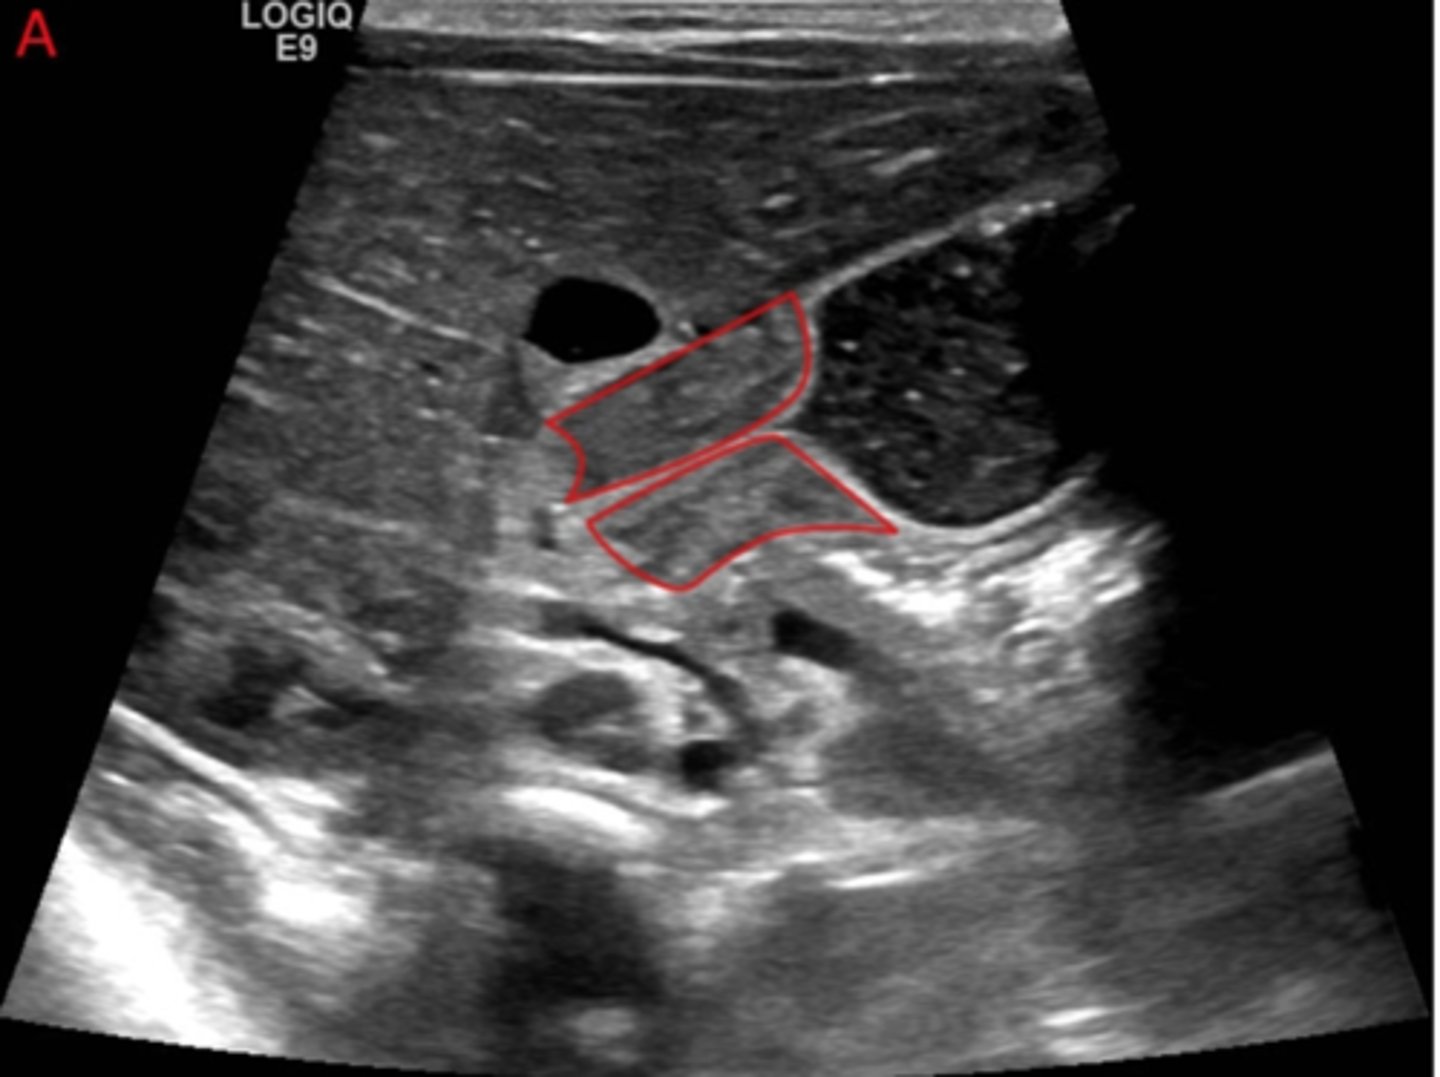

Hypertrophy and hyperplasia of the muscular layers of the pylorus --> leading to a functional outlet obstruction

Pyloric Stenosis

A 4-week-old male infant is brought to the pediatrician by his parents due to persistent vomiting. The vomiting began about 10 days ago and has become progressively worse. It is described as forceful and projectile, occurring shortly after feeds. The infant appears hungry after vomiting and wants to feed again. The parents have also noticed fewer wet diapers and some weight loss.

On physical exam, the infant appears mildly dehydrated. A firm, mobile "olive-shaped" mass is palpated in the right upper quadrant. No distention or tenderness is noted.

What tests should you order to further evaluate this infant?

What is the diagnosis?

What is the treatment?

1.) Ultrasound is most common test ordered.

UGI series will show string sign.

2.) Pyloric Stenosis

3.) Treatment

- Surgical

-Rehydration

Most common cause of intestinal obstruction in infancy*

Pyloric Stenosis